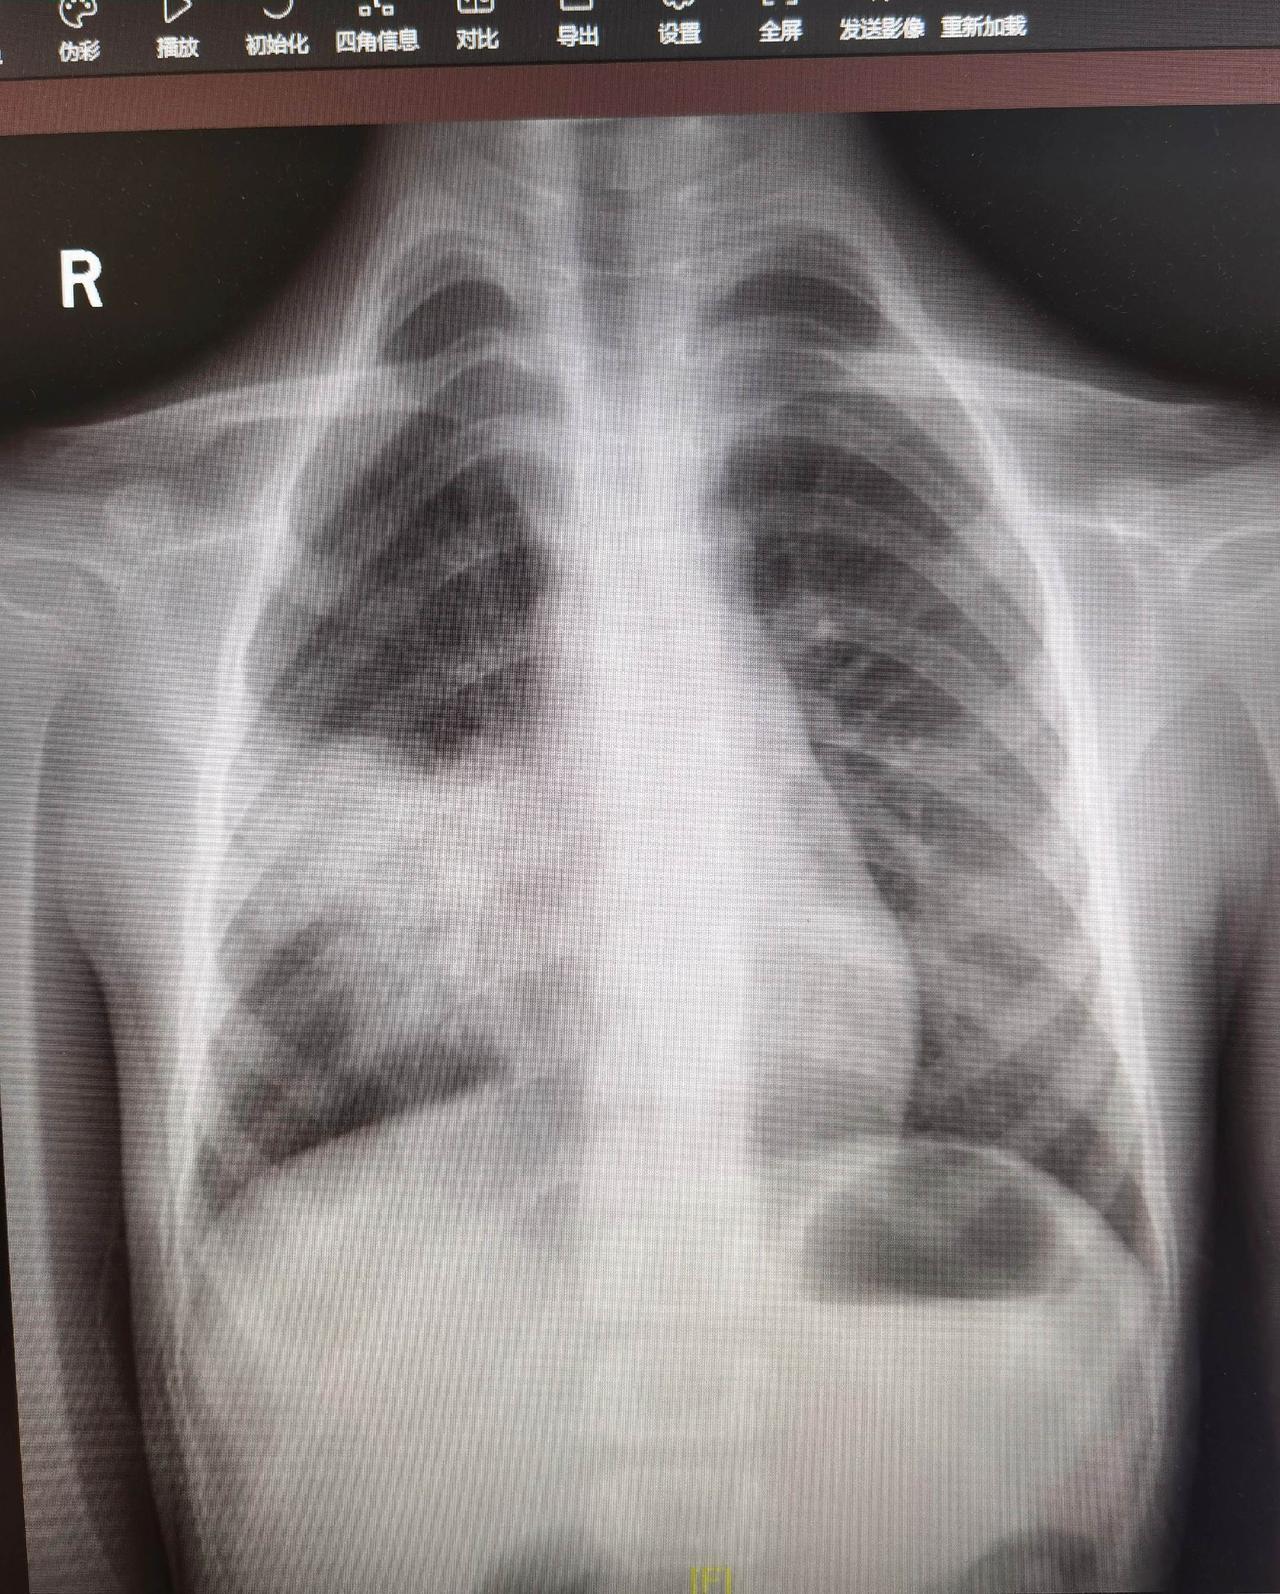

12岁女孩,初中生,间断发热七天。病初高热就确诊流感,吃了奥司他韦有改善,但还没完全退烧家长就让孩子上学去了,药物也是时用时不用。 期间退烧两天,后咳嗽突然加重并再次高热,一边上学一边吃退烧药扛,第三天就受不住了,来就诊,结果肺炎。合并肺炎支原体感染。 只能住院了。 关于流感退烧后再次发热,考虑以下几种情况。 1.用药疗程不足。奥司他韦抗病毒的机制是抑制病毒复制,常规疗程五天,提前停药可能会导致病毒在体内再次复制,所以疾病反复,出现发热。 2.出现其他并发感染。在疾病期和恢复期,机体免疫力相对较低,如果接触了其他病原体,极易合并感染。在学校,环境相对密闭,人群密集、防护欠缺,病毒种类仅次于医院,很难避免感染。 3.流感并发症。少部分人流感后会出现一系列的并发症,如气管炎、肺炎、心肌炎、脑炎等等。一旦出现,可能会再次发热,同时伴随其他相应的临床症状。 4.甲流急性期的反复高热,导致体温调节中枢功能紊乱,出现了短时间的低热。这种情况一般不会伴随其他不适,宝宝一般情况好,精神胃纳也不错,大多不需特殊处理,会自行恢复。 近期,各类病原体流行,感染后的并发症、后遗症等等问题频发,各位家长需高度警惕。 流感 肺炎支原体 肺炎